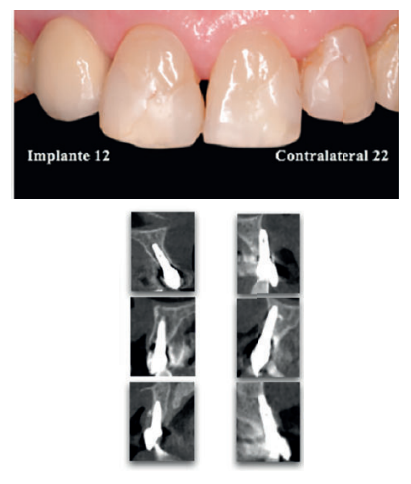

En referencia a los conocimientos obtenidos en artículos científi cos 4,8-19, se llevó a cabo un protocolo que consistió en la realización de un TAC acotado al sector anterosuperior y fotografías intraorales (Figura 2), para valorar los parámetros de PES, relacionándolo posteriormente con lo la identifi cación o no de tabla ósea vestibular en el TAC. Al fi nalizar, cada participante rellenó mediante una EVA un cuestionario de satisfacción con tres ítems: 1) Grado de conformidad con el tratamiento; 2) Cumplimiento de las expectativas esperadas; 3) Satisfacción respecto al resultado estético final.

En aquellos implantes que presentaban tabla ósea, el PES se cifró en 10,4 ± 2,3 puntos, superior al 6,6 ± 2,4 en casos de ausencia de tabla ósea (Figura 4). Las medianas difi rieron en cinco puntos, con un valor de 11 en presencia de tabla y valor de 6 en casos de ausencia. La magnitud de la diferencia fue signifi cativa p<0,001.

En la Figura 5 se observa una agregación de todas las variables del PES/Tabla ósea. El color del tejido peri-implantario y la formación de papila distal fueron las variables más asociadas a la identifi cación de tabla ósea (p<0,015). También, de forma signifi cativa el zénit y el margen gingival (p<0,05). La papila mesial exhibió también una fuerte tendencia (p=0,082).